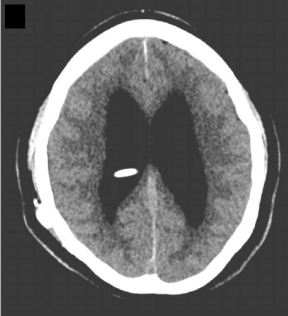

Exame de imagem abaixo:

Referência: doi: 10.1542/pir.2015-0134